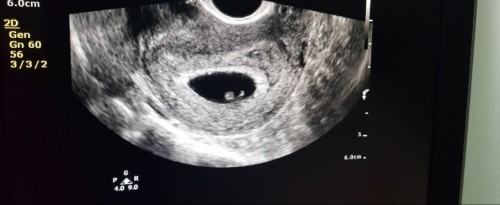

ท้องสอง8W พบภาวะแท้งคุกคามแม่มีตกขาวสีน้ำตาลออกกระปริบกระปอย แบบนี้น้องจะปลอดภัยไหม

สอบถามแม่ๆในนี้หน่อยค่ะใครเคยพบปัญหาภาวะแท้งคุกคามแบบนี้บ้างคะ น้องจะปลอดภัยดีไหม แม่มีโอกาสจะได้ตั้งครรภ์ต่อไปไหม หลังจากมีอาการตกขาวสีน้ำตาลได้สามวันแม่ไปหาหมอซาวน์ล่าสุดยังพบตัวอ่อนของน้องและเสียงหัวใจเต้น หมอให้หยุดพักนอนนิ่งๆ1สัปดาห์ แต่ตกขาวสีน้ำตาลก็ยังออกมาอยู่เรื่อยๆ แม่แอบห่วงน้อง และเป็นกังวลมากค่ะ #ขอคำแนะนำหน่อยค่ะ #คุณแม่ๆช่วยแนะนำหน่อยค่ะ #ขอบคุณสำหรับคำตอบค่ะ